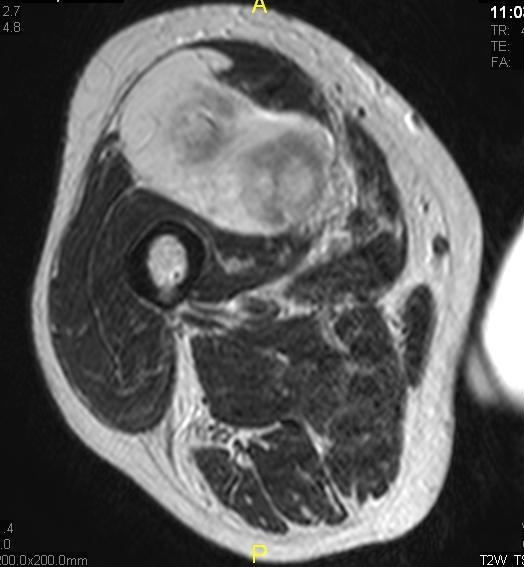

Fig. 3 Axial fat suppressed T2-weighted MR image demonstrates a large heterogeneous mass with multiple thick internal trabeculations. Fatty areas suppress on T2 weighted fat suppressed areas

Fig. 10 Axial T2 weighted MR image demonstrates a large well encapsulated heterogeneous mass with multiple thick internal trabeculations located in the anterior compartment of the thigh.